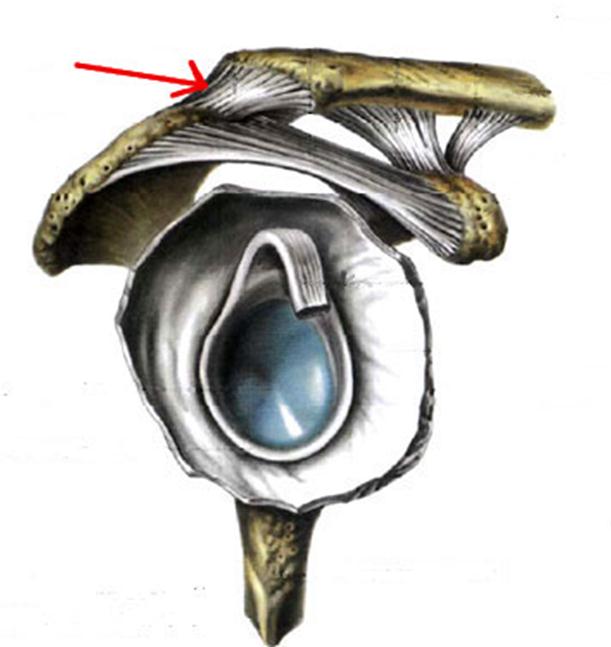

S: Стрелка указывает на lig....

-: acromioclaviculare

-: coracoacromiale

-: trapezoideum

+:conoideum

-: transversum scapulae superius